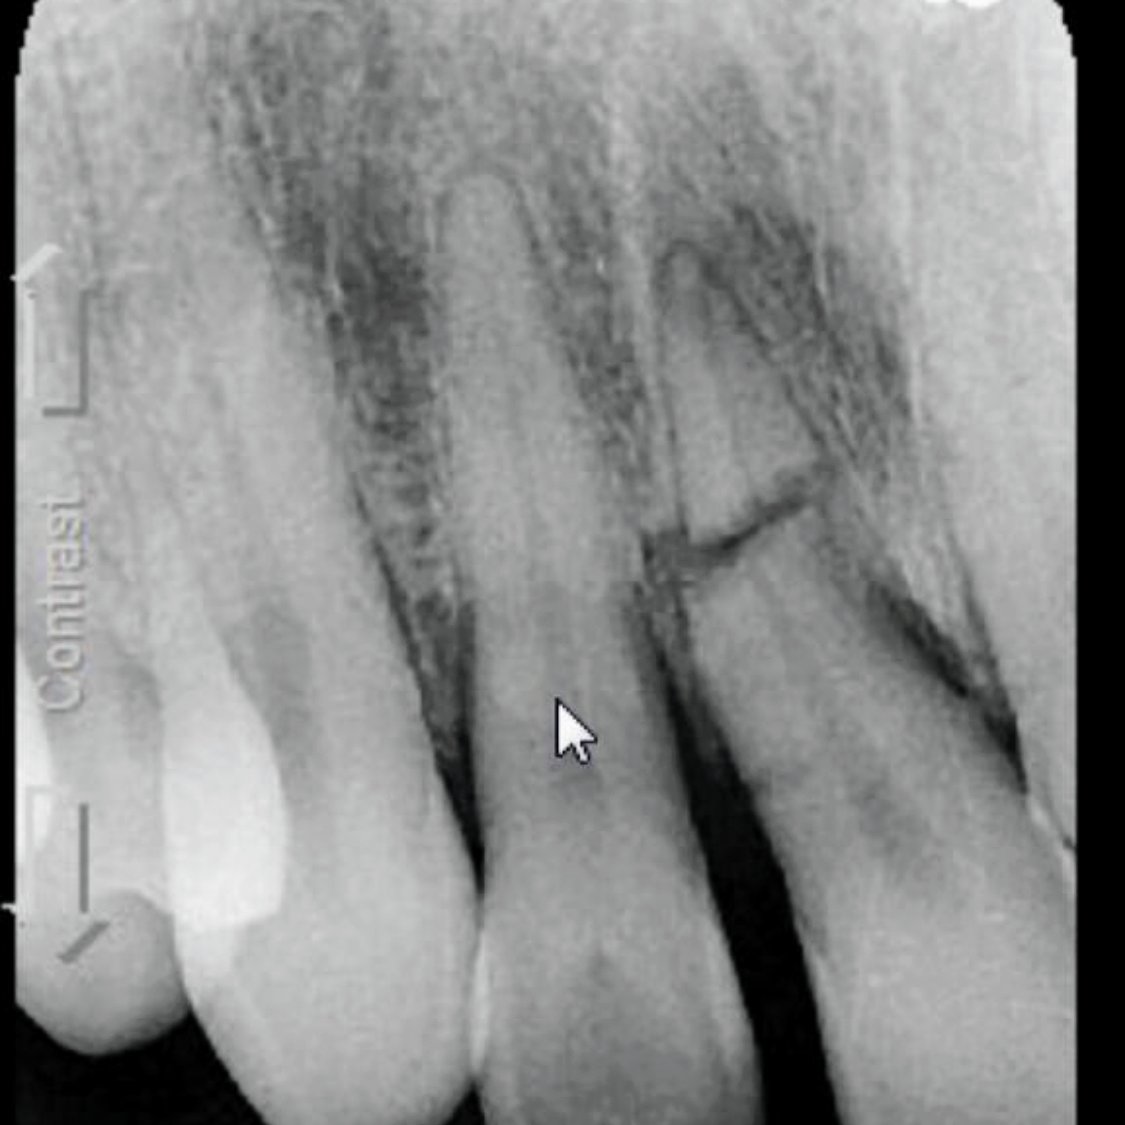

The practice distinguishes itself through its commitment to providing compassionate, personalized care in a state-of-the-art facility. Emergency Dentist NYC utilizes advanced technology including computerized tomography (CT) scanning, digital impressions, and implant placement systems to deliver precise diagnoses and customized treatment plans. The dental cone beam CT scanner enables the team to generate detailed 3D images of teeth, gums, nerves, and jawbone, ensuring thorough assessment of complex dental conditions.